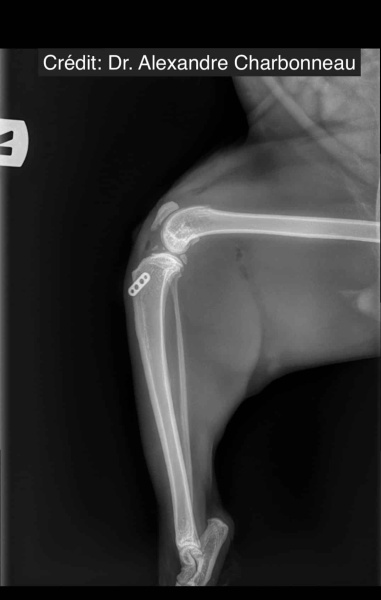

Radiologické snímky